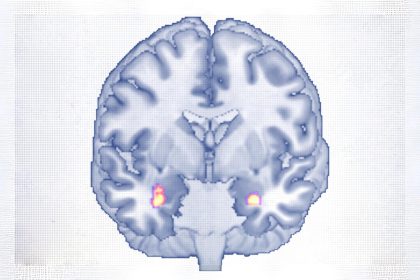

Voyager est une expérience exaltante, mais souvent éprouvante pour le corps. Les longs vols, les aliments inhabituels, les changements brusques de…